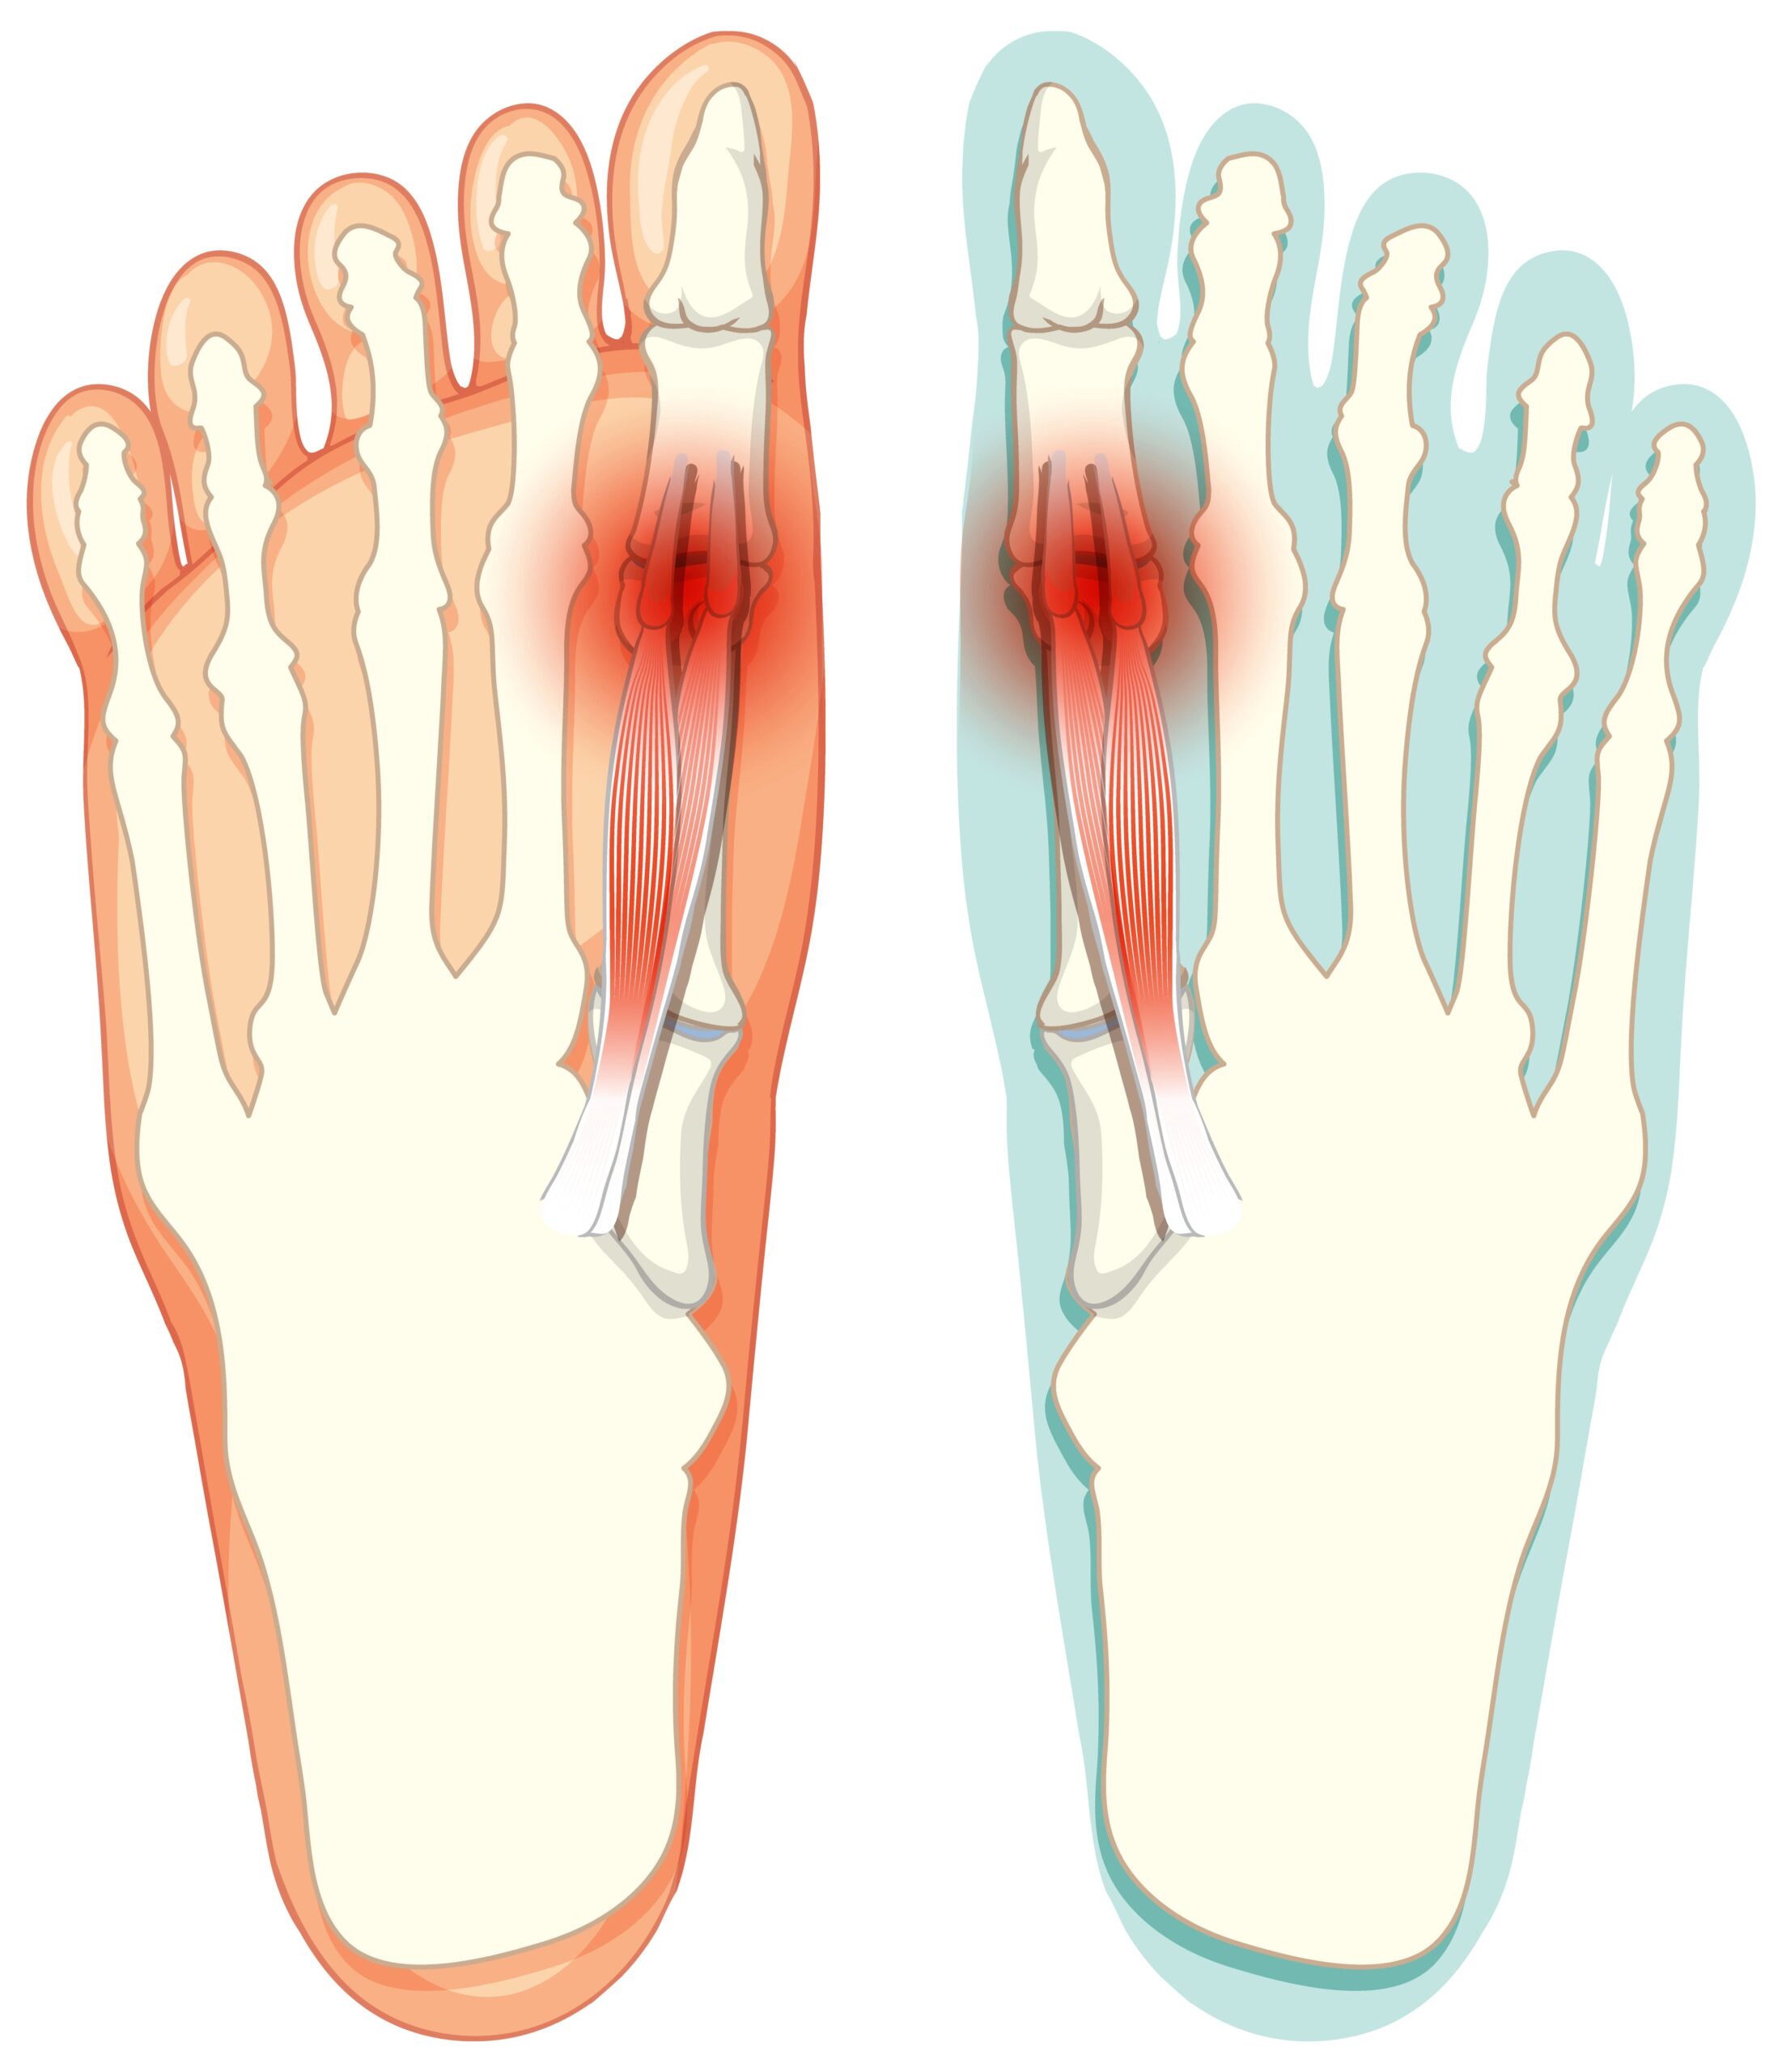

האם אתם מרגישים כאב חד בבסיס הבוהן הגדולה בכל פעם שהרגל "דוחפת" את הרצפה להליכה? אם הבוהן שלכם איבדה את הגמישות שלה ואתם סובלים מנוקשות (ולעיתים נפיחות מעל המפרק), כנראה מדובר בהלוקס ריגידוס (Hallux Rigidus) – שחיקה ניוונית של המפרק. במצב זה, מדרס רך "רגיל" לא יעזור, ולעיתים אף יחמיר את הכאב. אתם צריכים פתרון שימנע מהמפרק להתכופף.